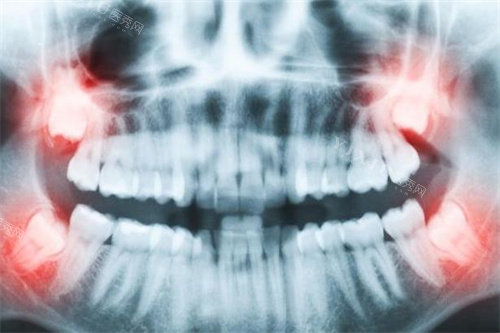

矫正前的准备工作十分重要。齐全的口腔检查是基础,需要处理现有的龋齿、牙周炎等问题。影像学检查如全景片、侧位片和CT扫描能帮助医生制定更准一些方案。取模或智能化扫描记录初始牙齿状态,为后续结果对比提供依据。与医生充分沟通期望和顾虑,确保双方对治疗目标有共识。